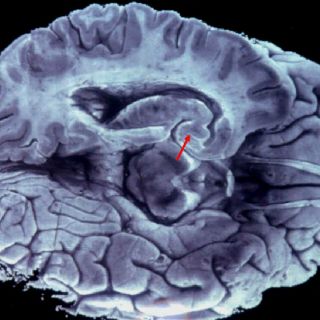

La aplicación directa del sistema estimula las áreas del cerebro dañadas

La aplicación de una corriente eléctrica en el cuero cabelludo para estimular las áreas del cerebro dañadas podría ayudar a las personas que han sufrido un derrame cerebral, según este nuevo estudio de la Universidad de Oxford (Reino Unido).